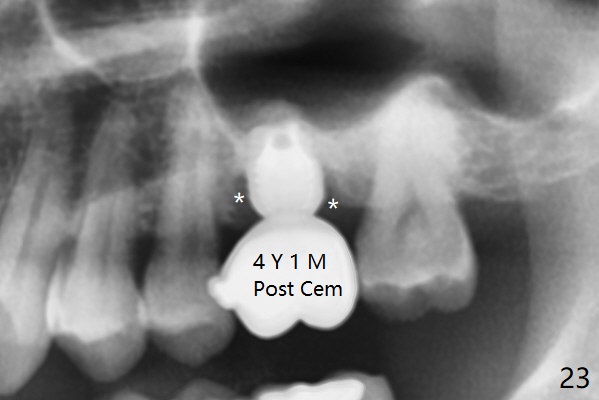

A 45-year-old man has lost the tooth #14 for a while (Fig.1); bone height is 5.4 mm. An extra wide and short implant is planned. Torus palatinus is large, suggesting that bone density should be high. A 6 mm tissue punch is chosen, but it is placed more palatal. If it were placed in the middle of the ridge, there would be no buccal keratinized gingiva (incision may avoid this issue). Additionally, the buccal portion of punch is made incomplete so that there is pedicle on the buccal side when the flap is raised (Fig.4,8: F). It is expected that the excess portion of keratinized tissue will form thick gingiva buccally. Osteotomy proves that bone is dense (Fig.2 (4.5x11 mm tap). Typical sinus lift is finished with placement of 6.4x6 mm (extra wide) bone-level implant (Fig.3, >55 Ncm). Following further torque, Fig.4 shows that the implant (I) is sub-gingival (<). Bitewings are taken to confirm that the implant plateau is at the crestal level (Fig.5,6 ^). PA shows sinus lift (Fig.7 *). The lingual aspect of the implant and healing abutment (H) is further bone grafted and covered by collagen dressing (Fig.8 *). The wound is protected with perio dressing. When the latter dislodges 7 days postop, the collagen dressing and bone graft are lost as well (Fig.10), while the buccal flap remains vital (Fig.9). The lingual exposed plateau should be able to heal normal. The collagen dressing should have been fixed in place by suture or as simple as a dental floss. There is mild nasal hemorrhage 1-2 days postop, possibly related to sinus membrane perforation and inability of Collagen Dressing to cover the perforation and contain the bone graft. When the patient returns for #9 implant placement in 3 weeks postop, the buccal flap reduces in size (Fig.11 *), while the palatal wound has healed with minimal exposure of the implant (Fig.12). Sinus graft remains in place 3 months postop (Fig.13); the buccal flap appears to have incorporated into a part of the gingiva (Fig.14). The bone density of the sinus lift appears to increase 10 days later when an abutment is placed (Fig.15 *). Although oral hygiene is pristine, there is apparent crestal bone resorption 12 months (Fig.16) and 20 months (Fig.17) post cementation, probably due to unfavorable crown/implant ratio and bruxism as well as pre-implantation bone loss (Fig.18,19). In contrast, an immediate implant in the same patient avoids pre- or post-implantation bone loss. In fact both the soft (Fig.20) and hard (Fig.21) tissues remain healthy 2 years 8 months post cementation. The sinus lift remains 3 years 8 months post cementation (Fig.22), while the crestal bone loss persists. The patients keeps complains of food impaction distal associated with bad smell 4 years 1 month post cementation. In fact the distal proximal contact is within normal limit. The bad smell is probably due to crestal bone loss (Fig.23 (pan), 24 (CT) *) and periimplantitis. Bone graft, PRF and Cytoplast membrane will be needed and fixed in place with long healing screw. When the patient returns for crown redo, he also reveals floss related gingival hemorrhage. There is pain associated with palatal sulcus probing with light gingiva erythema. Review of CT coronal section shows possible palatal (Fig.25 P) bone loss (*).